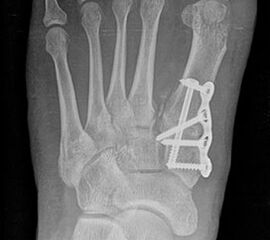

Bezüglich der Operationstechniken wird von früher häufig durchgeführten alleinigen Weich­teileingriffen am Großzehengrundgelenk aufgrund hoher Rezidivraten abgeraten 15. Die Operation nach Mc Bride mit lateralem Release, Exzision des lateralen Sesambeins, Abtragen der Pseudoexostose, Sehnenetransfer des M. adductor hallucis und mediale Kapselraffung zeigte unbefriedigende Mittel- und Langzeitergebnisse 16. Die Cerclage fibreux (mediale Kapselraffung) und das laterale Kapselrelease wird heute in Kombination mit einem knöchernen Eingriff angewendet. Bezüglich des Einsatzes von minimalinvasiven Operations­techniken vor Wachstumsabschluss liegen bisher keine Daten vor. Alle Osteotomien lassen sich nach Bedarf miteinander kombinieren. Es ist darauf zu achten, dass Osteotomien keine offenen Wachstumsfugen verletzen.

• Medial zuklappende Grundphalanxosteotomie nach Akin 17

• Subcapitale distale Chevron Osteotomie nach Austin 18

• Diaphysäre Osteotomie

• Scarf 19

• Ludloff 20

• Proximale Metatarsale I Osteotomien 21

• medial aufklappend – verlängernd

• lateral zuklappend – verkürzend

• bogenförmige Crescentic Osteotomie

• proximale Chevron Osteotomie

• proximale Verschiebeosteotomie

• medial aufklappende Cuneiforme I Osteotomie 1522

• Wachstumslenkung: Hemiepiphysiodese der lateralen Basisfuge am Metatarsale I  23

• Nach Schluss der Wachstumsfugen: TMT I Arthrodese nach Lapidus 2425